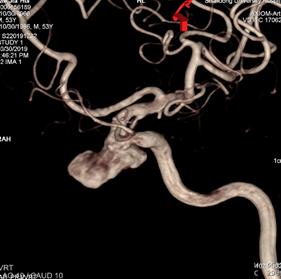

重新行3D造影,根据目标动脉瘤及载瘤动脉选择角度,路图下在0.014 Synchro2微导丝引导下将WILLIS®覆膜支架(4.5*16mm)准确定位至左侧颈内动脉C3动脉瘤位置。

3D重建图示支架贴壁良好。